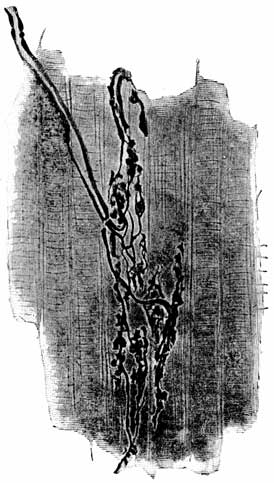

Fig. 10 (Spalteholz). A view of the lower part of the trachea, dividing into the main bronchial tubes, which again branch into a tree-like form. The air-cells are built up around the terminations of the finest bronchial tubes, of which they are a sort of membranous extension.